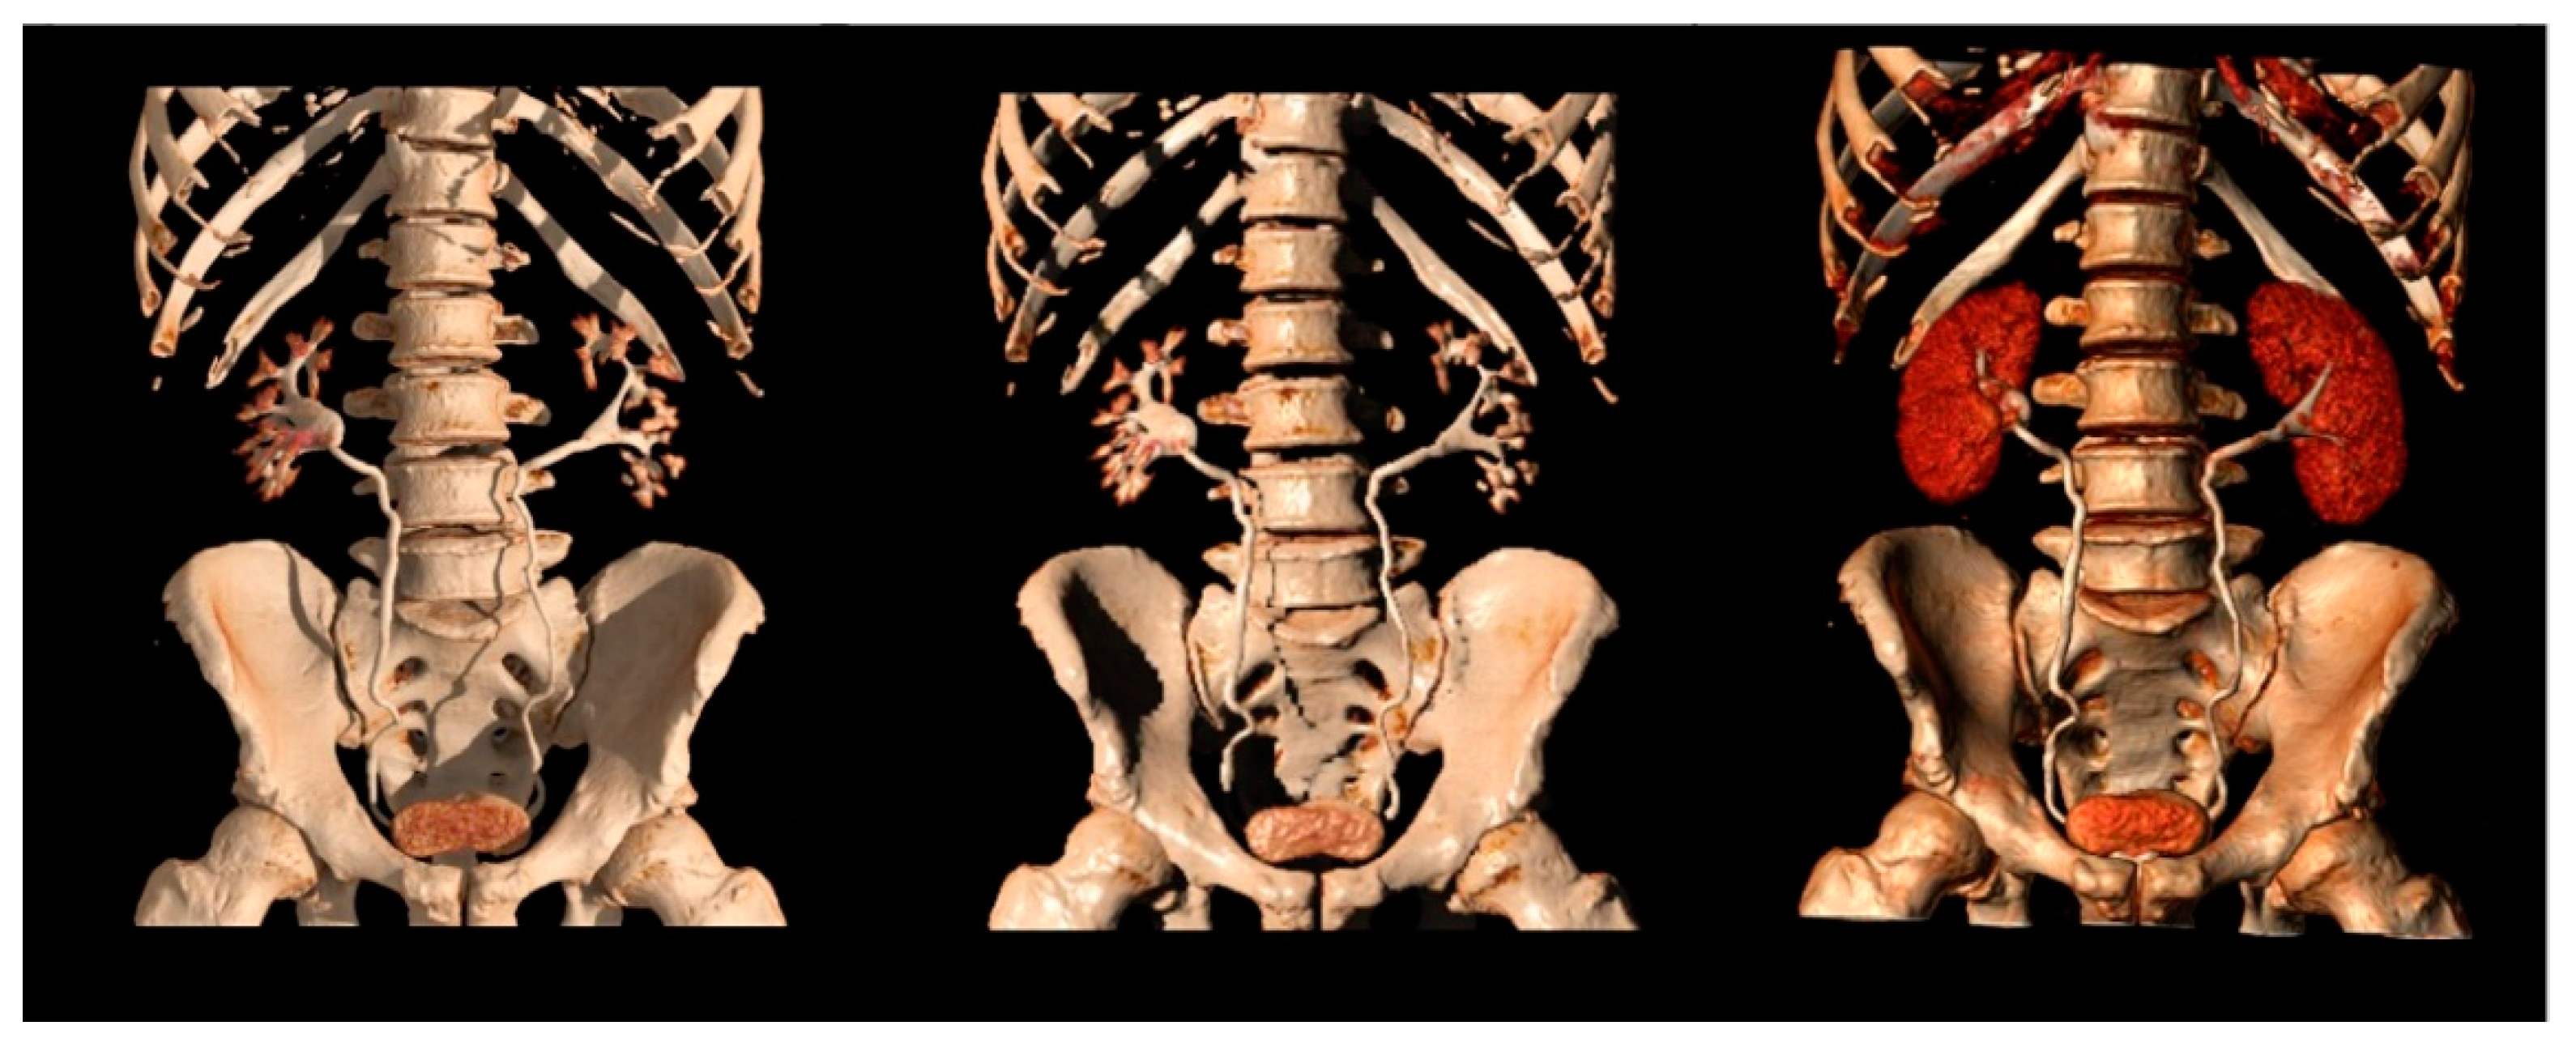

Native thin (0.5–0.75 mm) axial images are usually submitted to coronal and sagittal reformations, then further to MIP and 3D reconstructions (Figure 7).

Figure 7.

Different 3D reconstructions of the excretory phase.

MIP reformations are constructed from the highest attenuation voxels in a dataset and projected into a 3D format. These reconstructions are particularly helpful in evaluating the collecting systems and ureters, allowing a complete and quick overview of the high-density contrast within the collecting systems, and highlighting subtle filling defects, focal thickening of the excretory system walls, luminal narrowing or strictures, calyceal abnormalities, hydronephrosis, and hydroureter.

Three-dimensional reconstructions provide specific colors to each voxel in a data set according to its attenuation and relationship to other adjacent voxels, allowing the visualization of the whole opacified excretory system. Some authors support their role in the identification of slight urothelial thickening, especially in cases of reduced excretion of the contrast into the collecting system, when MIP reformations are of limited usefulness [7,19,46].